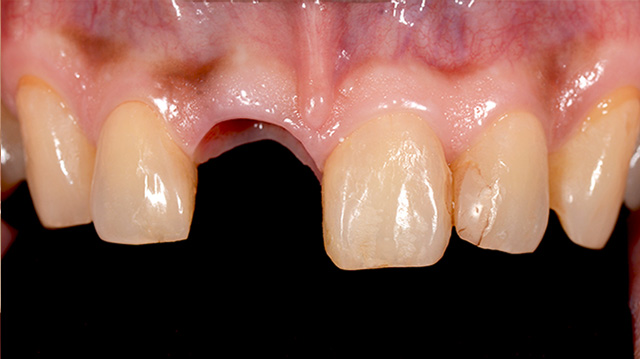

| 年代・性別 | 30代 男性 |

|---|---|

| 主訴 | 前歯の色が気になる |

| 治療期間 | 約1年 |

| 費用 |

仮歯 5,500円 × 2 ジルコニアクラウン 176,000円 × 3 インプラント 300,000円 インプラント仮歯 22,000円 サージカルガイド 70,000円 |

*キャンセルポリシーをご一読のうえご予約ください